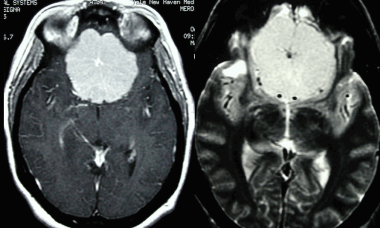

Рентгенография при менингиоме

В большинстве случаев обзорная рентгенография черепа не обладает диагностической ценностью, поскольку не позволяет получить никаких данных, которые могли бы указывать на наличие менингиомы. Иногда могут отмечаться кальцифицированные участки или зоны реактивного гиперостоза. В редких случаях могут быть видны участки остеолиза.

8. На рентгеновском снимке во фронтальной плоскости хорошо заметно кальцифицированное образование в области лобной пазухи. На снимке в латеральной проекции образование визуализируется кверху от решетчатой пластинки. Несмотря на то, что по результатам исследования можно заподозрить, обнаруженные признаки неспецифичны, и поэтому обнаруженное внутричерепное образование требует дообследования при помощи КТ.

Большинство рентгеновских снимков не отображают признаков наличия заболевания. Менингиомы типа en plaque характеризуются диффузным гиперостозом, чаще в области крыла клиновидной кости и птериона. Такие результаты исследования с большой долей вероятности свидетельствуют о наличии

болезни.

Кальцинаты внутри опухоли являются значительно более редким рентгенографическим проявлением менингиомы; это зачастую приводит к ложно-отрицательным результатам. Большинству пациентов не проводится рентгенографическое исследование, поскольку диагноз был подтвержден при помощи КТ или МРТ.